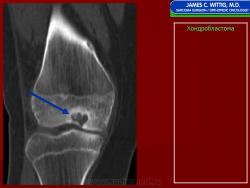

Хондробластома — это редкая доброкачественная опухоль, локализующаяся, главным образом, в эпифизе и отличающаяся своеобразным клеточным составом. Ткань новообразования представлена овальными, округлыми и веретеновидными клетками, напоминающими незрелые хондроциты (хондробласты). Зрелый гиалиновый хрящ определяется лишь в некоторых опухолях. Возраст больных варьирует. Мужчины поражаются в два раза чаше женщин. Пациенты предъявляют жалобы на боли в течение нескольких месяцев или лет, у некоторых больных определяются внутрисуставной выпот, припухлость и ограничение движений. Наиболее типичная локализация опухоли — проксимальные эпифизы плечевой и большеберцовой костей, а также дистальный эпифиз бедренной кости. У 20 % больных опухоль развивается в плоских или коротких трубчатых костях, преимущественно в пяточной и таранной. Изредка поражаются кости лицевого черепа, в том числе височная. В большинстве случаев новообразование выходит за пределы эпифиза и распространяется на метафиз. На фоне остеолиза обнаруживаются рассеянные участки обызвествления в виде пунктирных линий, а также разреженный трабекулярный рисунок. Хондробластома, как правило, не выходит за пределы кости, но изредка проникает в полость сустава. В процессе роста опухоли иногда возникает вторичная аневризматическая костная киста.

Рентгенологически хондробластома представляет собой сравнительно большой (2-4 см) очаг округлой формы, четко отграниченный от окружающей кости склеротической каймой. На фоне очага в большинстве случаев, но не обязательно определяются плотные включения, напоминающие хлопья ваты.

Рентгенологическая картина. Хондробластома выглядит как небольшой, от 3 до 6 см литический очаг, центрально или эксцентрично расположенный, с четкими контурами, занимающий около половины площади эпифизарной зоны. Хондробластома плоских костей и мелких трубчатых костей больших размеров, может сопровождаться припухлостью мягких тканей, вздутием кости и периостальной реакцией. Распространение процесса на метафизарную зону встречается часто.